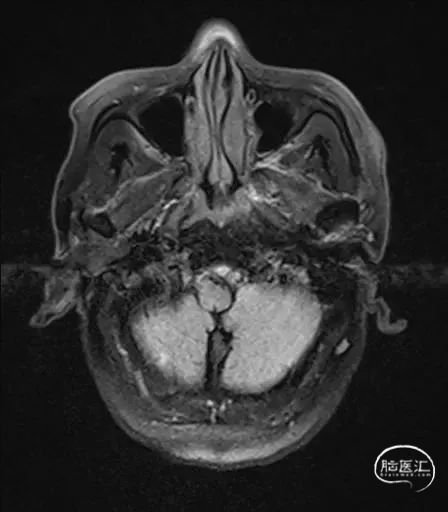

MRI提示小脑缺血性改变。

术后9天MRI:

术后CT:未见明显脑出血,双侧小脑低密度影。